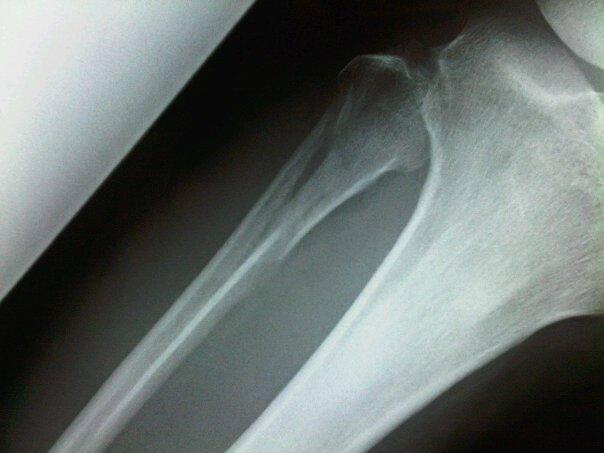

↑

こちらは、腓骨側。くっつきまひた。